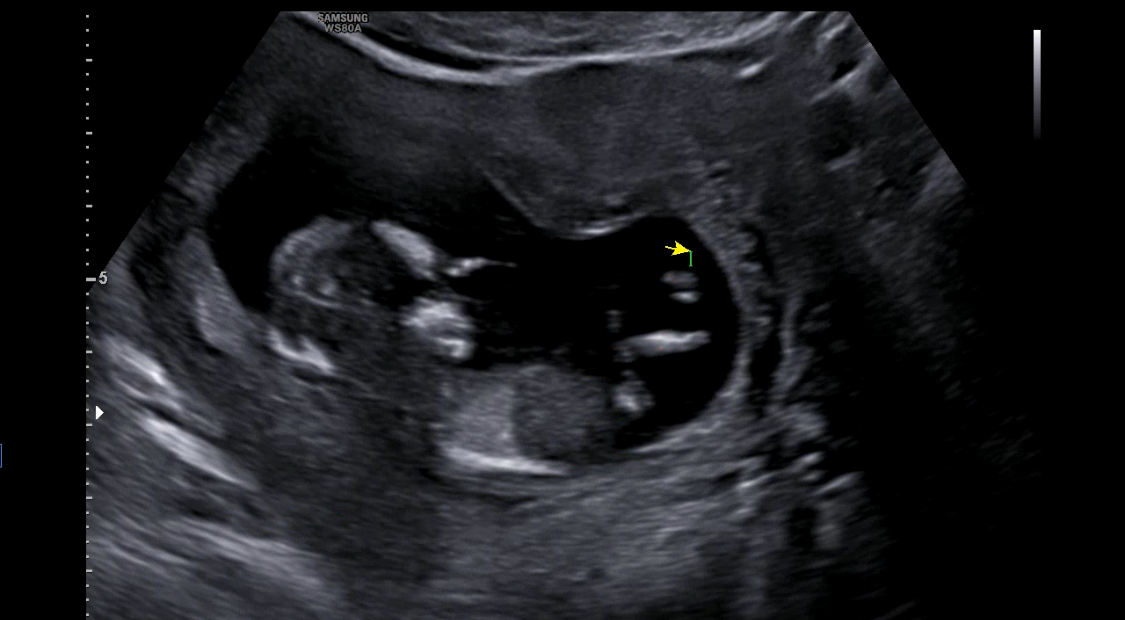

그리고 2층으로 올라가 정밀초음파를 진행했는데요,,! 고은빛은 초음파 봐주시는 선생님이 따로 계시더라구요.

오늘은 첫 정밀초음파다보니, 목투명대도 재야하고, 콧대도 봐야하고,, 했는데 뽀동이가 너무 얌전히 있더라구요ㅠㅠㅎㅎ

열심히 자세도 바꾸고, 기침도 해보며 결국 모두 확인했고 정상,,! 소견 받았습니다ㅎㅎ 다행이야,,

콧대?는 0.18cm, 목투명대는 1.52cm였어요!